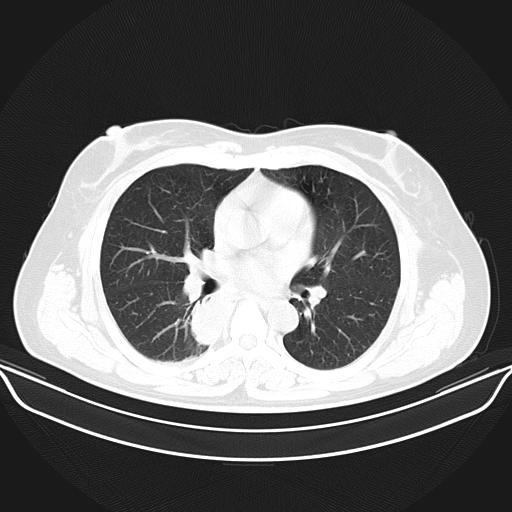

标题: CT22224:肺部肿块

f,48,主因咳嗽咳血来我院检查,无发热。

1)右肺下叶背段团块状软组织密度影;建议抗炎治疗后复查排除肿瘤性病变。2)右侧少量胸腔积液。

谈一谈个人的看法:机器性能应该不错,可惜扫描方法不太正确,即没有及时薄层扫描图像,也没有增强检查,这样的检查方法不正确的图片拿来研究只能是猜一猜:右肺下叶阻塞性改变,建议进一步检查删除肺癌。

支气管镜检查未见异性细胞,抗炎治疗20天,肿块明显缩小。